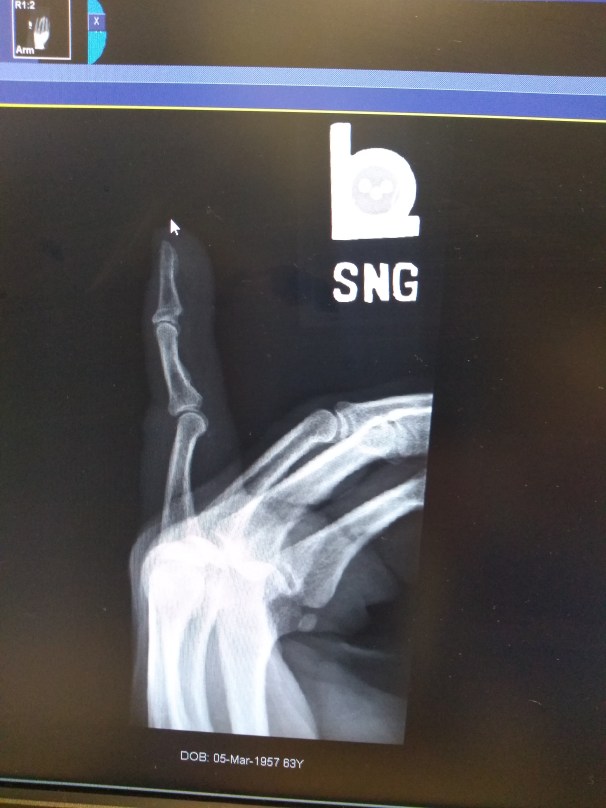

After a couple X-rays it was confirmed, severe dislocation. Since a doctor wasn’t available, the PA would be doing the fixing. I got ready and he pulled. I just about came off the table. Hell, that hurts. Three more attempts and I told him to Fuck Off, I couldn’t do another one. It was still out, but closer. Lidocaine, injected into the base of the finger in a ring block, was the next step. Damn, I was almost ready to give up whatever secrets they thought I was hiding. While a nurse held my arm down, he went for it again, and again, and one more time before another X-ray. It was close, but because of swelling and a couple bone chips, that was as close as he could get it. Time for a splint and to go back to the hotel.